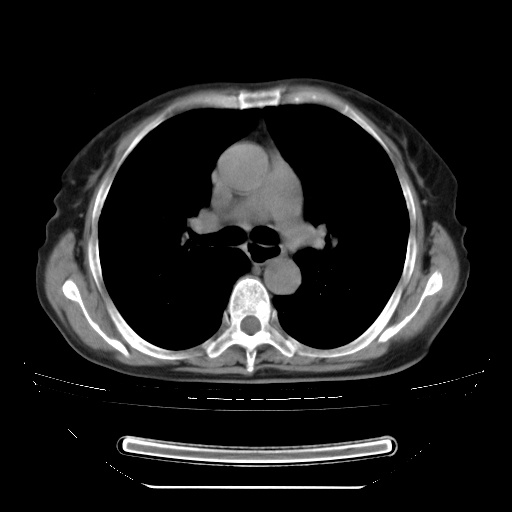

两肺内病灶呈小结节状和树芽状,纵膈的肿大的淋巴结密度不均匀,并见有钙化,考虑为两肺结核可能更大些。

两肺内病灶呈小结节状和树芽状,纵膈的肿大的淋巴结密度不均匀,并见有钙化,多形态病灶,考虑为两肺结核,肝内考虑小囊肿。

增殖性多发性病灶,大小不一,分布不均匀,发生于肺泡中,纵隔淋巴结肿大其内有钙化,诊断:细支气管肺泡癌,

病灶以结节为主,大部分边界清楚,分布不均,病灶形态较单一,偶见空泡征,纵膈淋巴结肿大钙化,无结核中毒症状考虑 感染性病变【真菌类可能性大】,细支气管肺泡癌。其他待排

片子很好,质量很高,两侧肺门淋巴结肿大并有钙化,两肺弥漫病灶,首先考虑tb并播散,但年龄大了呀(72岁)小细胞肺癌不能除外,如果是肺癌也没什么大的治疗了,建议正规抗结核治疗后复查

支持亚急型粟粒性结核

纵隔见肿大淋巴结并钙化,首先考虑结核,但感觉小结节像“挂果”征,分布位于支气管边缘,所以不排外肺泡癌,建议抗唠后复查吧?不然是癌的话,也不好治吧?化疗?

考虑两肺播散性肺结核(亚型),纵隔淋巴结结核。